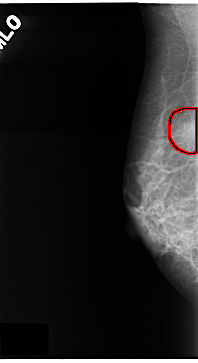

C_0134_1.RIGHT_MLO

RIGHT_MLO LINES 4712 PIXELS_PER_LINE 2568 BITS_PER_PIXEL 12 RESOLUTION 50 OVERLAY

FILE: C_0134_1.RIGHT_MLO.OVERLAY

TOTAL_ABNORMALITIES 1

ABNORMALITY 1

LESION_TYPE MASS SHAPE OVAL MARGINS ILL_DEFINED

ASSESSMENT 5

SUBTLETY 4

PATHOLOGY MALIGNANT

TOTAL_OUTLINES 1

BOUNDARY